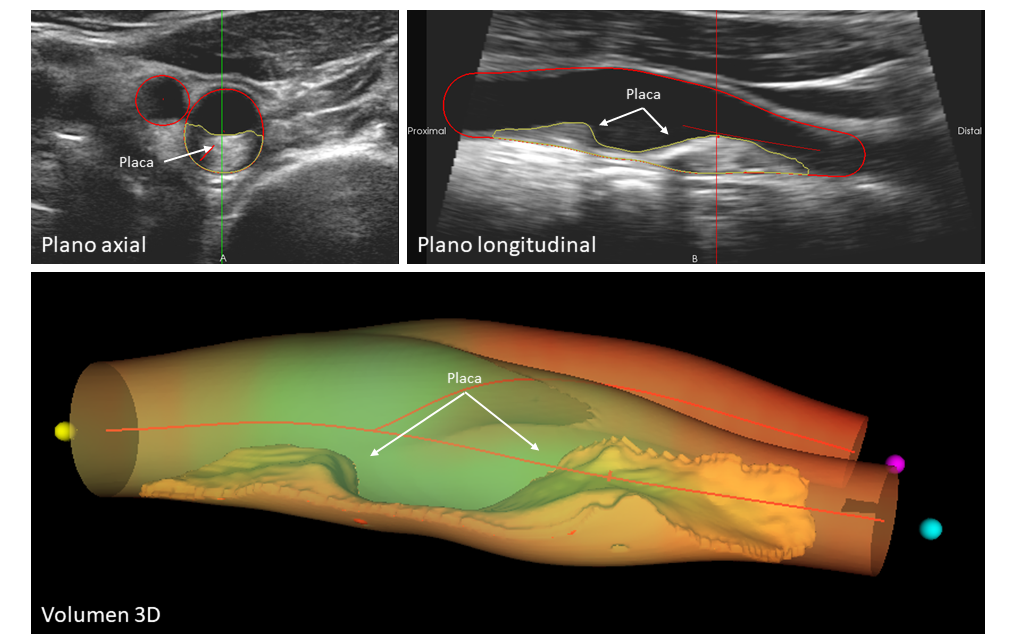

La imagen muestra un caso ejemplo de enfermedad ateroesclerótica que afecta a la arteria carótida. La vista axial (arriba a la izquierda) y longitudinal (arriba a la derecha) presentan una placa visible de gran tamaño y su extensión. La representación volumétrica en 3D (abajo) ofrece una visualización detallada y precisa de la placa, lo que permite una evaluación completa y exhaustiva de la enfermedad.